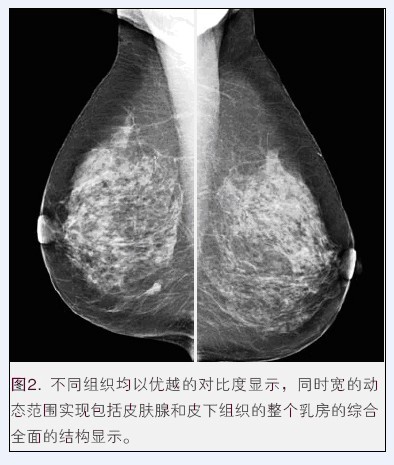

(普朗醫(yī)療品牌——BTX-9800高頻鉬靶乳腺X光機(jī)(乳腺X射線機(jī)))